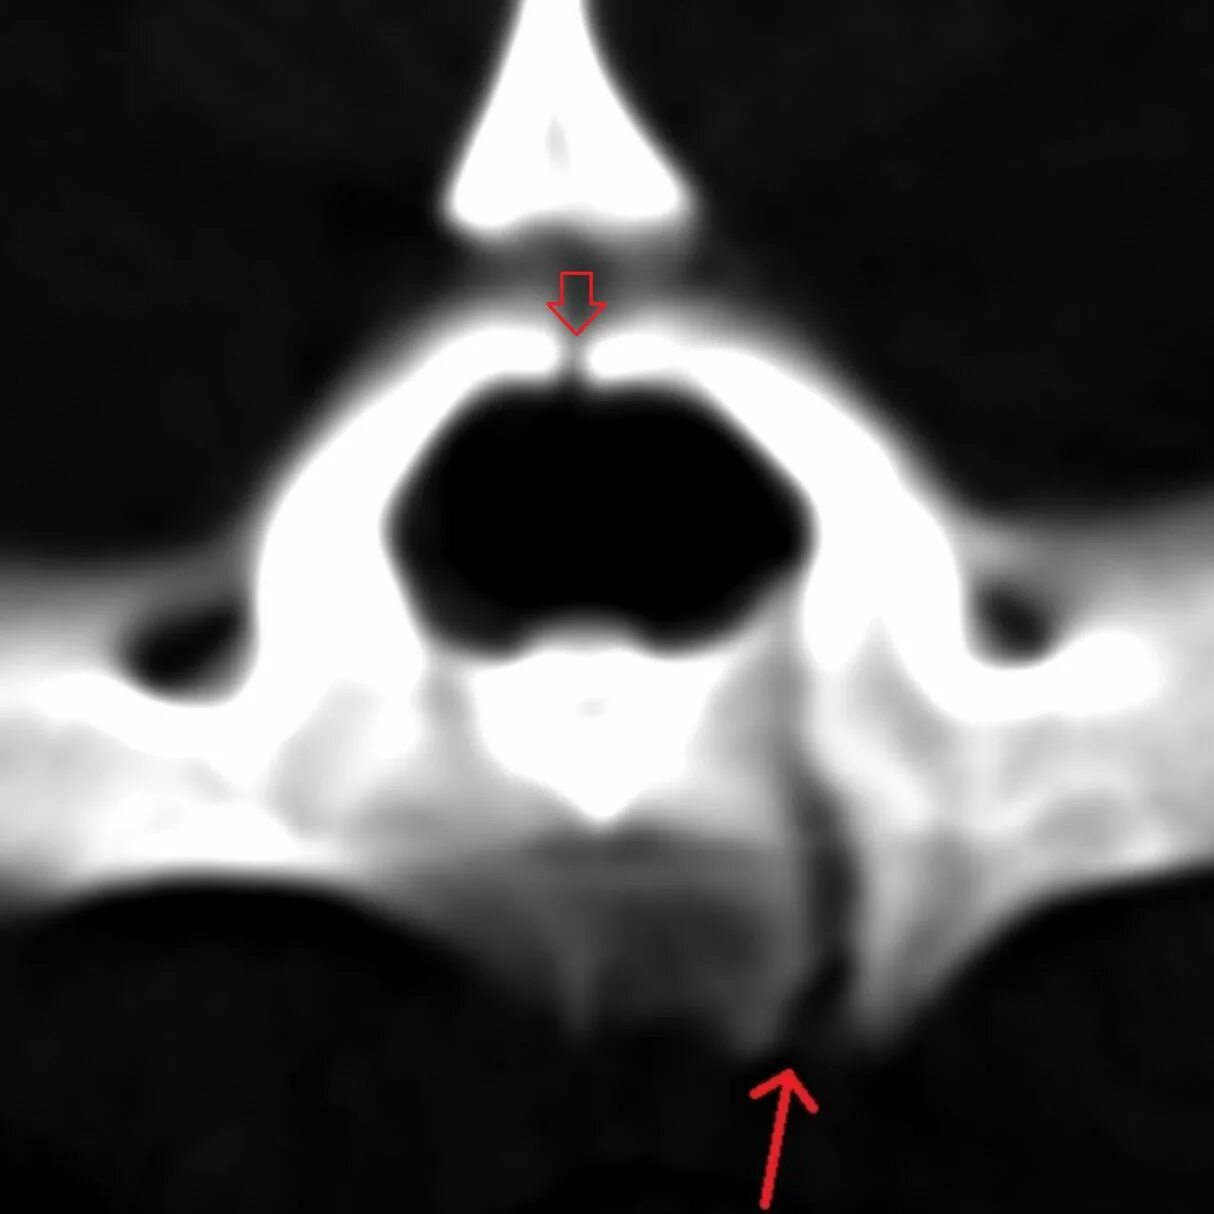

Атлант кт